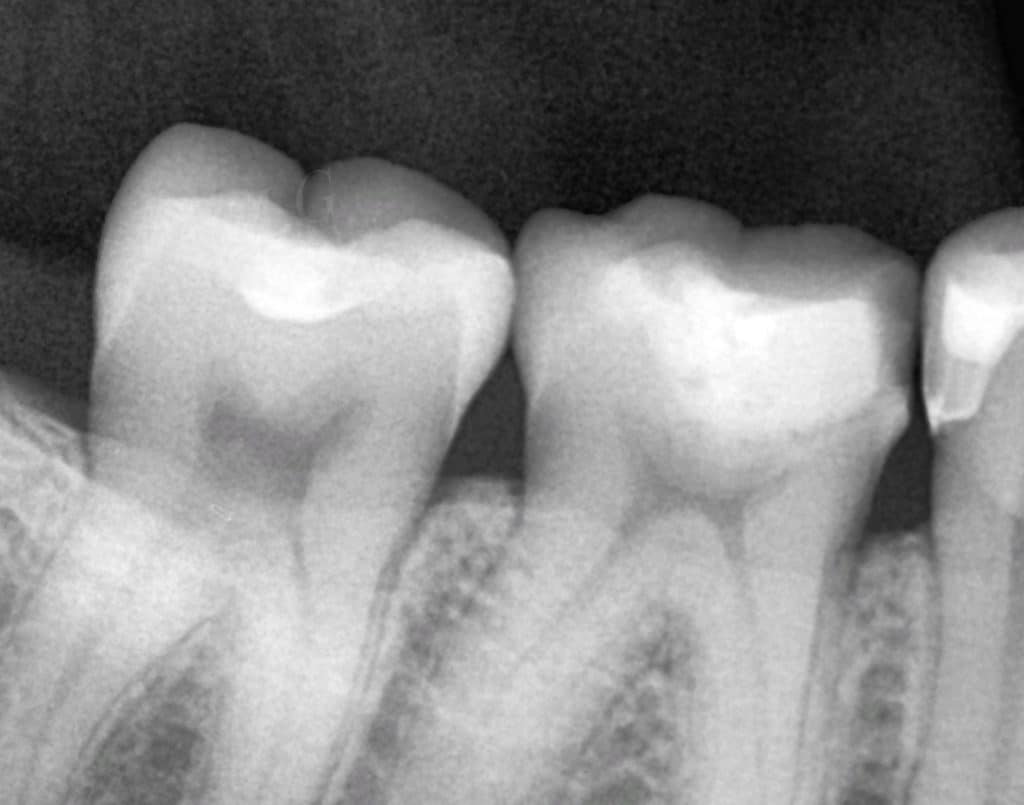

clinical examination revealed that old defective restoration and x ray showed recurrent caries under old restoration.

post operative x ray showing how sealed is the restoration & contour .